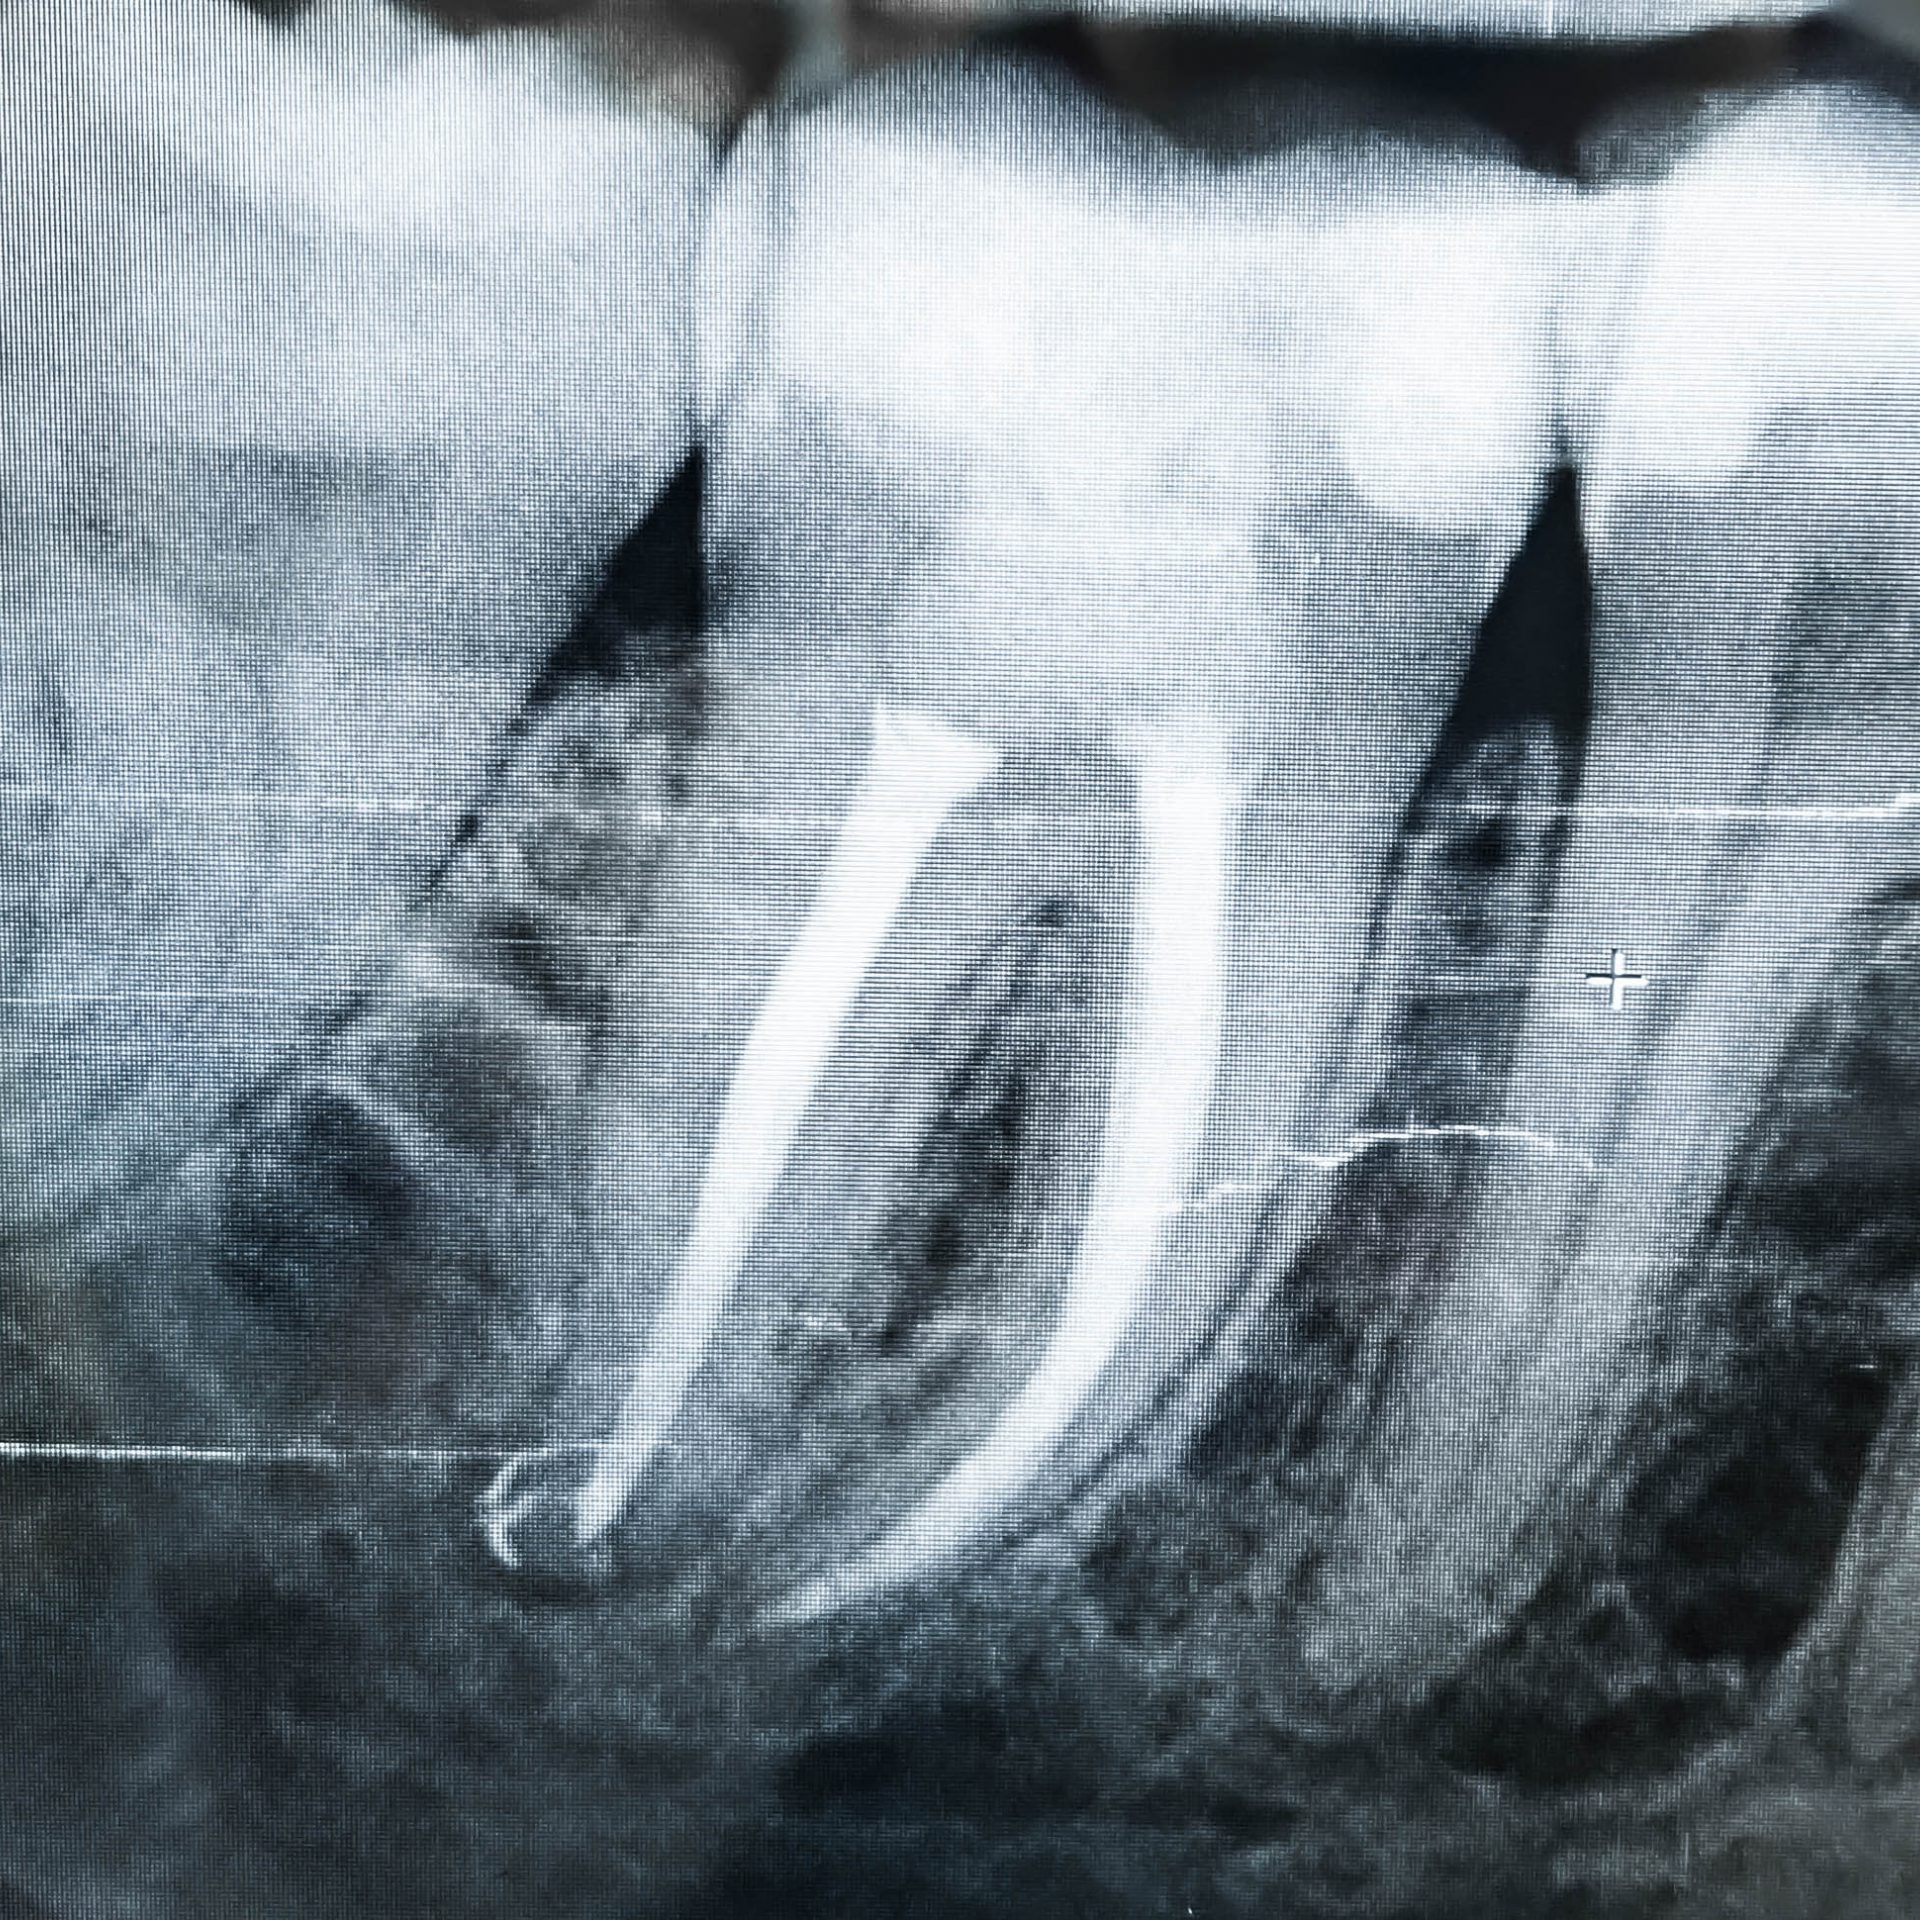

Wurzelkanalbehandlung / Endodontie

Bei starken pulpitischen Schmerzen oder radiologischen Auffälligkeiten kann eine Wurzelkanalbehandlung nötig sein. Durch das Einleiten einer solchen Behandlung können Zähne erhalten werden, die unter anderen Umständen gezogen werden müssten. Ob eine Wurzelkanalbehandlung möglich und sinnvoll ist, wird immer als Einzelfall mit dem Behandler besprochen und abgewogen.

3D Röntgen DVT

Für radiologische Untersuchungen mit speziellen Fragestellung im Dental- als auch HNO- Bereich, bietet das DVT (digitale Volumentomographie) das genaueste Aufnahmeverfahren. Die 3D Röntgendarstellung kann sowohl zur Fokussuche bei Beschwerden, Wurzelkanalbehandlungen als auch bei chirurgischen Planungen genutzt werden. Für eine chirurgische Behandlungsplanung mit Implantaten ist dieses Verfahren der neueste Standard.